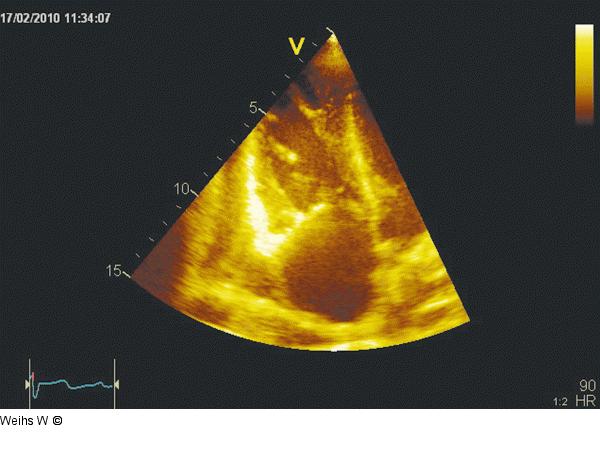

Abbildung 4: Apikaler 4-Kammerblick Modifizierter apikaler 4-Kammerblick mit Darstellung des rechten Herzens: Es stellt sich ein dilatierter und hyperkontraktiler rechter Ventrikel als indirekter Hinweis auf das Vorliegen einer rechtsventrikulären Volumenbelastung dar. Die Trikuspidalklappe, in diesem Schnitt mit dem anterioren und septalen Segel, ist starr und lässt eine regelrechte Koaptation der Segel in der Systole vermissen. Der rechte Vorhof ist stark dilatiert und balloniert als Hinweis auf eine massive rechtsatriale Druckerhöhung. |

Modifizierter apikaler 4-Kammerblick mit Darstellung des rechten Herzens: Es stellt sich ein dilatierter und hyperkontraktiler rechter Ventrikel als indirekter Hinweis auf das Vorliegen einer rechtsventrikulären Volumenbelastung dar. Die Trikuspidalklappe, in diesem Schnitt mit dem anterioren und septalen Segel, ist starr und lässt eine regelrechte Koaptation der Segel in der Systole vermissen. Der rechte Vorhof ist stark dilatiert und balloniert als Hinweis auf eine massive rechtsatriale Druckerhöhung. |